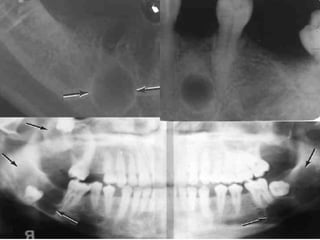

 Radiographic features:

 Unilocular or multilocular radiolucency with

a thin sclerotic border. Resorption of the

root adjacent teeth may sometime be

present.

Radiographic appearance

 The characteristic radiographic

feature is well circumscribed

radiolucent area (round or ovoid,

unilocular or multilocular) with

sclerotic border in place of normal

tooth